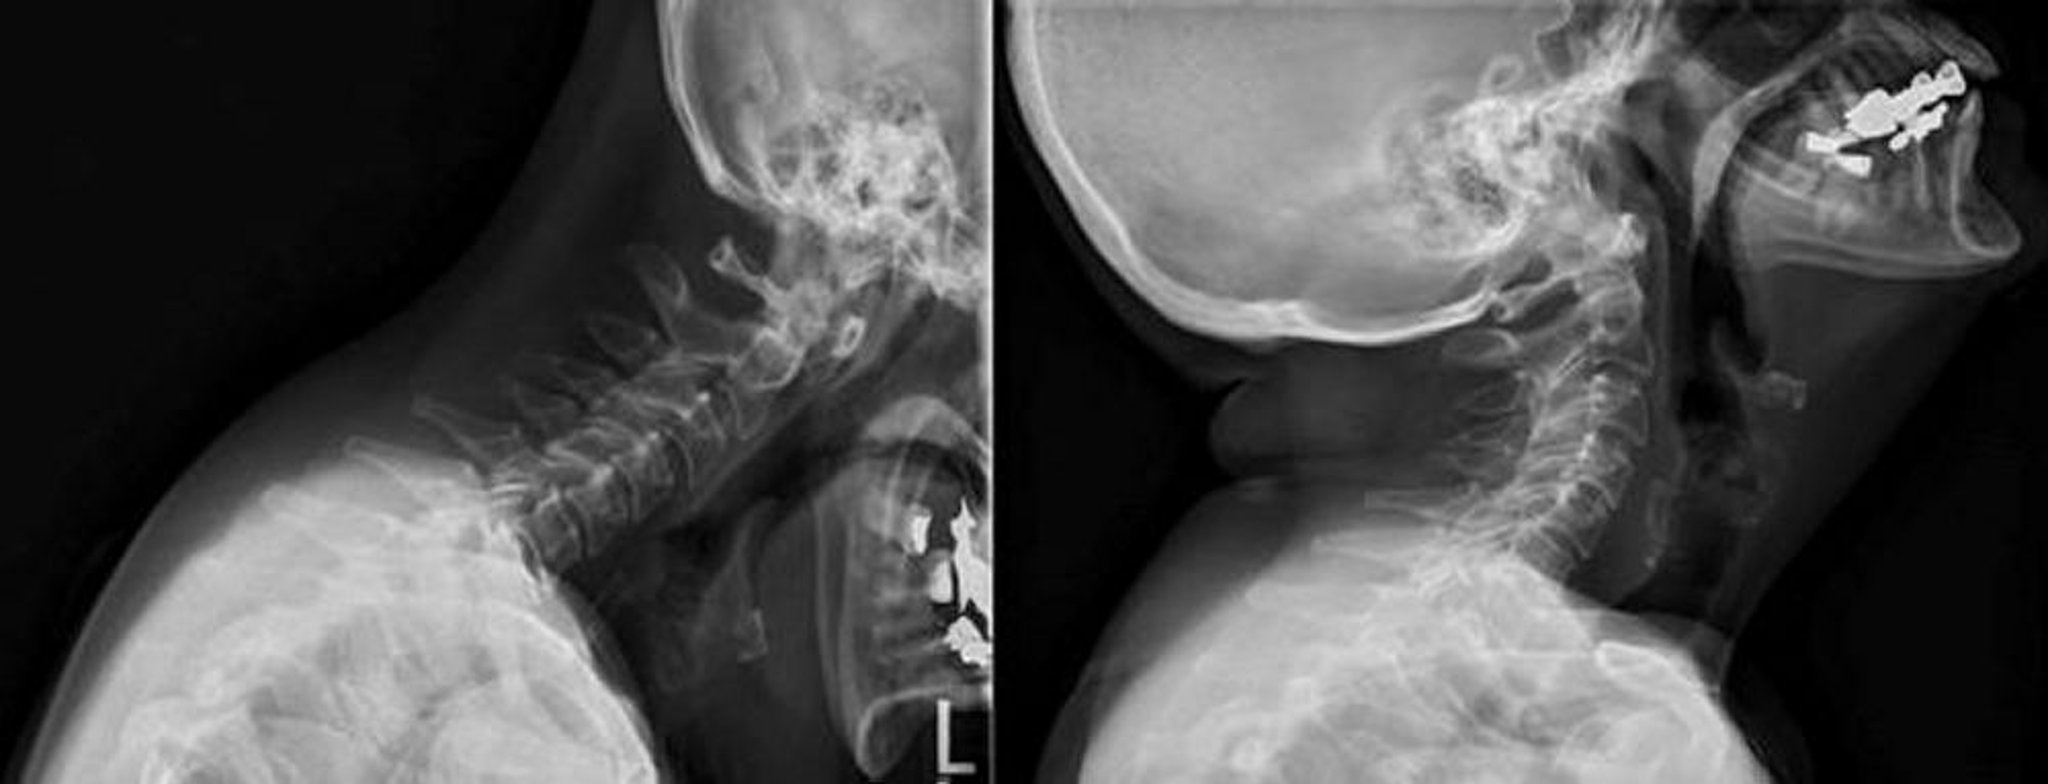

Поражение шейного отдела позвоночника при ревматоидном артрите

На данных рентгенограммах при сгибании и разгибании шейного отдела позвоночника показано увеличение атланто-аксиального расстояния, доходящее до 5 мм в проекции сгибания, которое уменьшается с разгибанием.

Image courtesy of Kinanah Yaseen, MD.